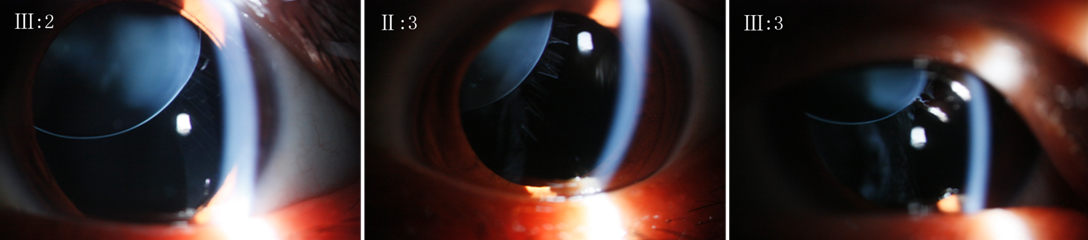

Figure 2 of Li, Mol Vis 2012; 18:504-511.

Figure 2. Slit lamp photographs of the right eye of the affected family members (III:2, II:3, and III:3 from left to right) after the pupils were dilated, showing ectopia lentis (superonasally).